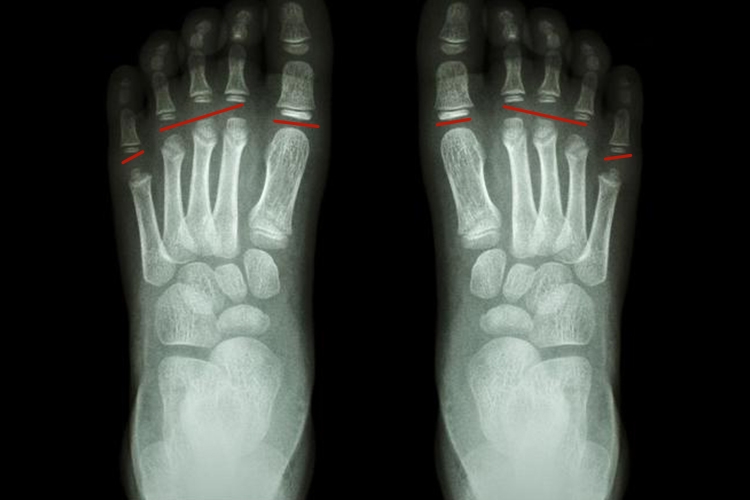

儿童足部骨骺在X线片上主要表现为骨骺线,未闭合时,X线可表现为较宽的横行透光带,闭合后可残留一条致密线。

骨骺是骨在发育过程中,骨两端的软骨中出现的骨化点。儿童长骨的骨骺未闭合时,X线片上表现为较宽的横行透光带,随着年龄增长而逐渐变窄,形成一条透光线,X线学上称它为骨骺线。最后,骨骺与干骺端进行骨性连接形成骨端,长骨停止生长,骨骺线随之消失,有时残留一条致密线痕迹。